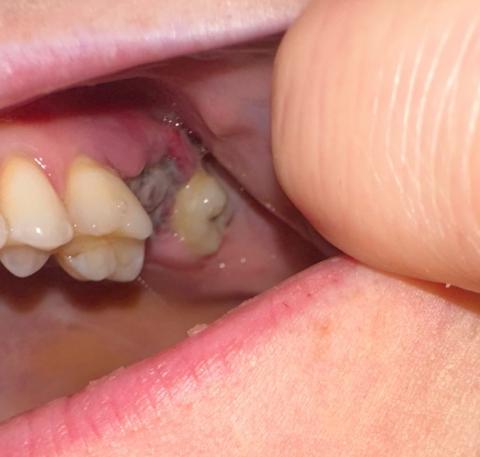

Quick visual impression (from the photo)

The socket shows a dark area in the extraction site — that can be a blood clot or residual blood/debris.

I don’t clearly see obvious pus or gross swelling in this photograph, but the image is limited (lighting, angle, saliva and soft-tissue can hide signs).

Because the extraction was just yesterday, it is very early to tell: normal early healing often looks like a dark/blackish clot in the first 24–48 hours.

From the photo alone (extraction yesterday) it most likely looks like a normal early clot — too soon to declare dry socket or infection.